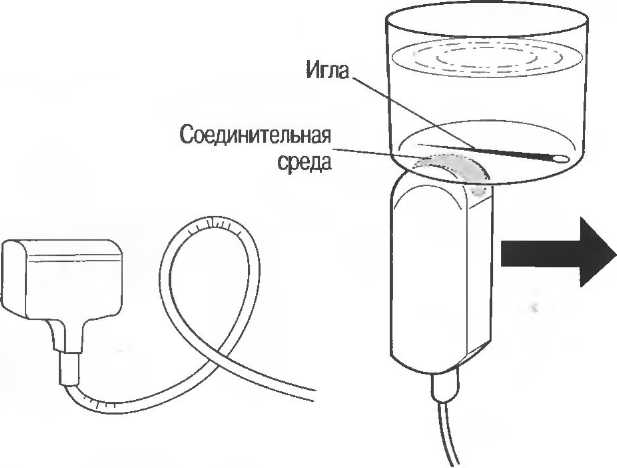

Секторный датчик может быть проверен при сканировании подкожной иглы через дно емкости, заполненной водой. Изображение иглы должно оставаться неподвижным, если игла неподвижна.

На практике, наиболее значимые в клиническом плане артефакты возникают при проведении биопсии или аспирации под контролем ультразвука. До тех пор пока кончик иглы не появится в плоскости сканирования на экране, он не будет визуализироваться, и может создаться ложное представление о том, что игла значительно короче (рис. 21в).

Рис.21 в. Изображение иглы в емкости с водой. Слева игла находится в плоскости сканирования не полностью, в результате чего выглядит короче, чем есть на самом деле (крестик определяет реальную глубину проникновения иглы). Справа игла визуализируется полностью.